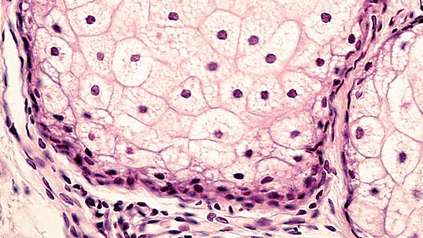

Science and Innovation

At the Wellcome Genome Campus we undertake both wet and dry lab science, basic research and the delivery of bioinformatics resources for the global scientific community.